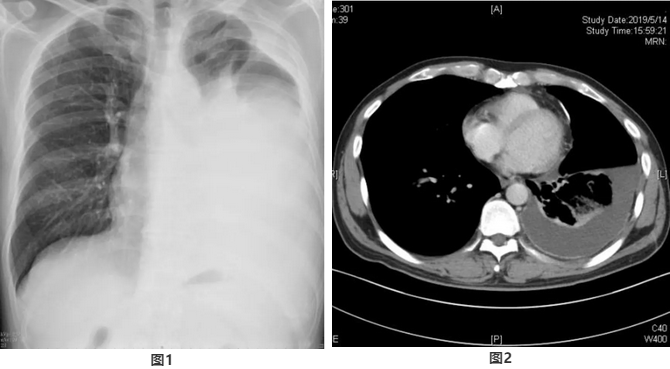

外院胸片显示左侧大量胸腔积液(图1),我院胸部增强CT显示左侧胸膜增厚(图2)。查外周血常规未见异常,血沉5mm/1h。多次查痰抗酸染色阴性,结核抗体阴性。